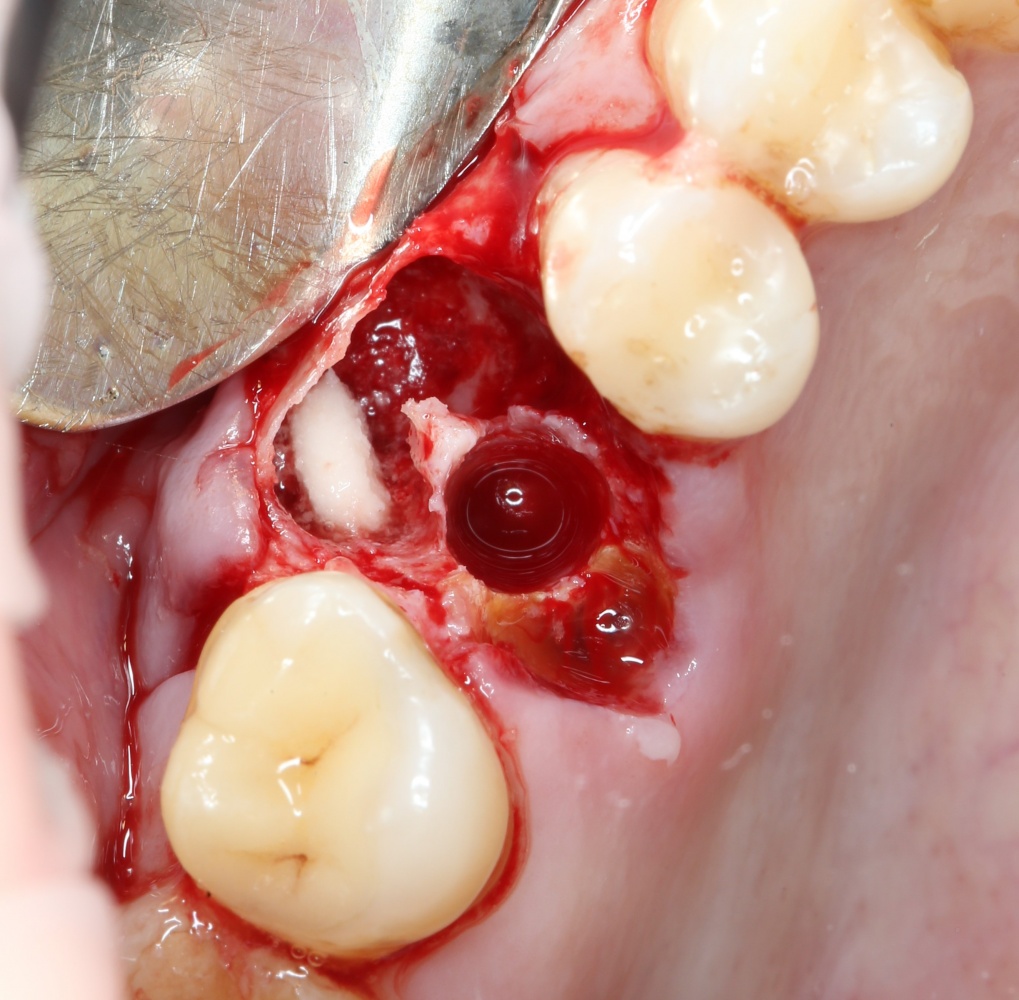

Вот ситуация:

По ряду причин, мы вынуждены удалить верхнюю шестерку и заменит ее на имплантат.

Все начинается с удаления зуба:

Обратите внимание на состояние вестибулярной стенки лунки. В проекции верхушек корней вы можете увидеть костный дефект, вызванный длительным воспалительным процессом (собственно, почему этот зуб пришлось удалять). В этом случае, вестибулярная стенка лунки неизбежно лизируется после удаления зуба, а это приведет не только к проблемам в эстетике, но и осложнит последующий уход за протетической конструкцией. Поэтому в данном случае мы должны продумать, в том числе, аугментацию лунки. И порядок действий здесь несколько иной, нежели в предыдущем случае.

Устанавливается имплантат Astratech (Dentsply Implants):

Для аугментации также используем Bio-Oss Collagen 100 mg, нарезаем его по размеру с помощью скальпеля и позиционируем в лунках щечных корней: